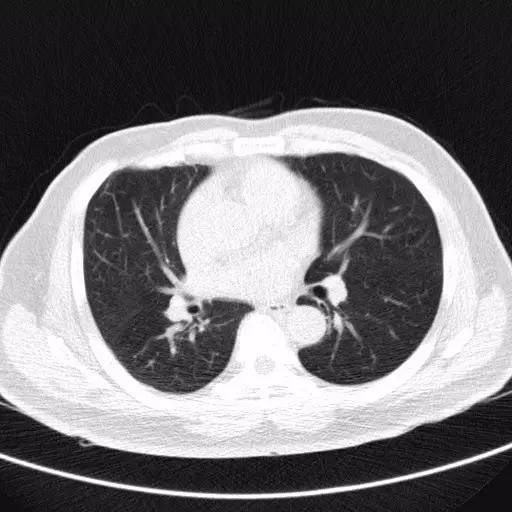

胸部CT

CT比胸片具有更高的灵敏度和特异度,能够显示小结节的二维形态,还能清晰显示小结节周围组织的影像学特点。胸部CT扫描不仅能够更清晰的观察肺部小结节的形态及大小,还能通过不同时间的CT图像动态的比较小结节的变化情况。胸部薄层CT具有更高的分辨率,应该作为评估肺部孤立性小结节性质的首选影像学检查方法。